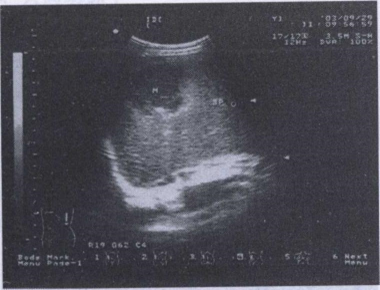

50.患者,女性,25岁。有痛经史,月经正常,突发右下腹痛,伴腹膜刺激症状,超声图像示盆腔内见一5cm囊性包块,边界不清,张力低,内见密集细小光点,伴周围积液。最有可能是()